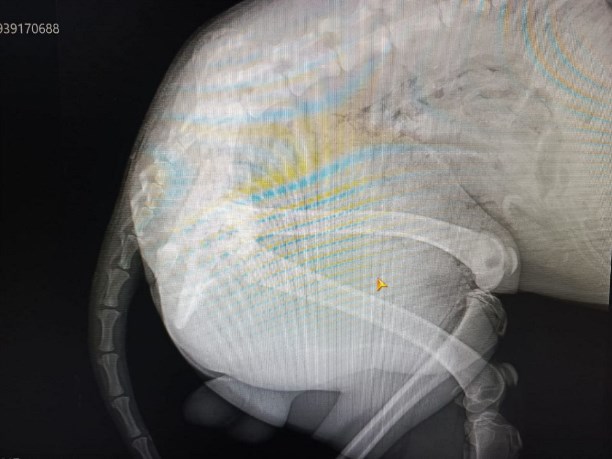

В Фонде помощи бездомным животным "Право на жизнь" сообщили, что у пса диагностировали перелом нижней челюсти, перелом локтевой и лучевой костей, пневмоторакс, контузия легких. После стабилизации состояния предстоит сложная операция.